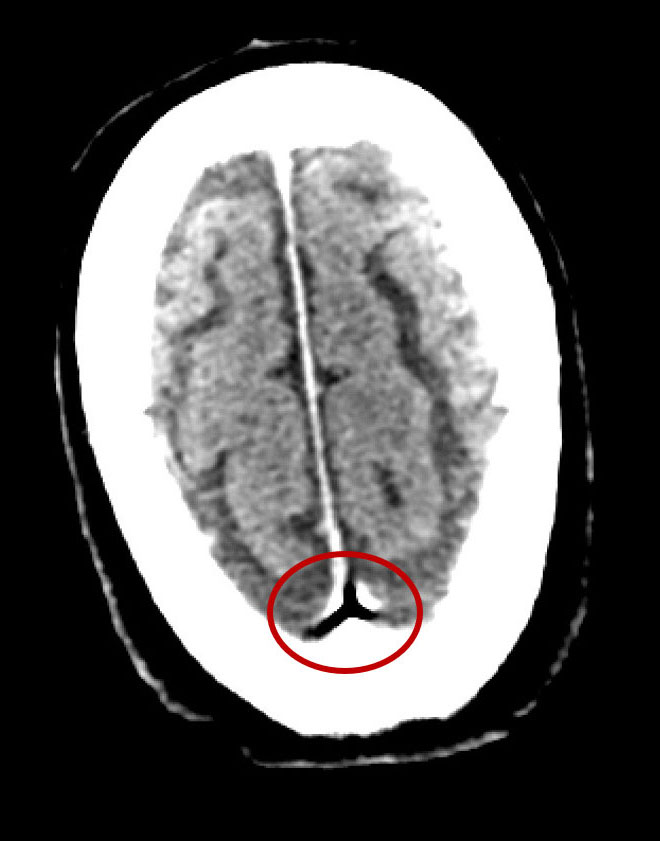

Non-contrast CT Brain:

Focus of air in the superior sagittal sinus